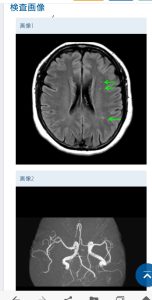

MRI所見で

脳委縮 脳梗塞 側脳室周囲高信号 白質病変

脳微小出血 脳出血 脳腫瘍 水頭症 頭頚部病変

MRA所見で

動脈瘤 不整突出瘤 動脈解離

血管屈曲・蛇行 狭窄度 血管閉塞 脳血管奇形

その結果がわかりやすく見れる。

今回の脳ドッグで未病が発見。

白質病変が0(病変なし)からⅣ(重度)の評価のうちⅠ。

Ⅰ~Ⅲは未病と呼ばれて病気に向かっている状態、ということらしい。